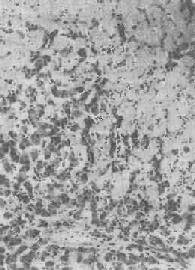

纤维瘢痕组织的玻璃样变

图1-19 纤维瘢痕组织的玻璃样变

胶原纤维变粗,互相融合呈均质梁状